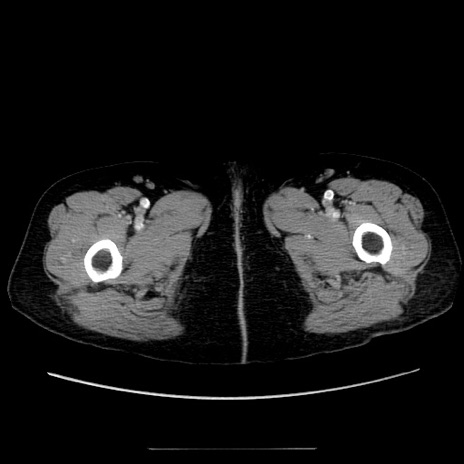

症例5(横断像)

【症例】70歳代女性

【主訴】お腹が張る

【現病歴】1週間くらい前から腹部膨満の自覚あり。昨日夜から増悪したため、本日救急外来受診。

【身体所見】意識清明、BT 36.5℃、BP 165/106mmHg、HR 80bpm、SpO2 98%、腹部:膨満、軟、自発痛・圧痛なし、触診にて不快感あり、腸蠕動音:減弱

【データ】WBC 12600、CRP 1.04